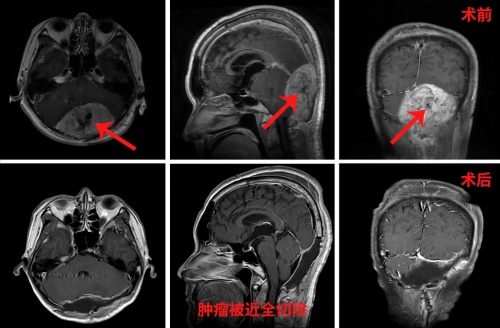

既是性命相托,定当全力以赴。10月21日,经过详尽的手术方案和充足的手术预案后,刘东被推入了手术室,在全麻状态下,张宏伟教授团队为其实施了“后正中巨大脑转移瘤切除术”。

术中,张宏伟教授不急不躁,步步为营,极其耐心地一点点分离肿瘤界面,同时细心止血……分离肿瘤与硬膜、神经组织、血管后,最终将肿瘤近全切除。下午6时许,走出手术室的那一刻,张宏伟长长地舒了一口气,手术圆满成功,术中出血约650ml,患者安返ICU重症监护室进行监护。术后患者不久恢复清醒,自我感觉头脑较前更清醒,语音、语速恢复较好,各项功能正常。